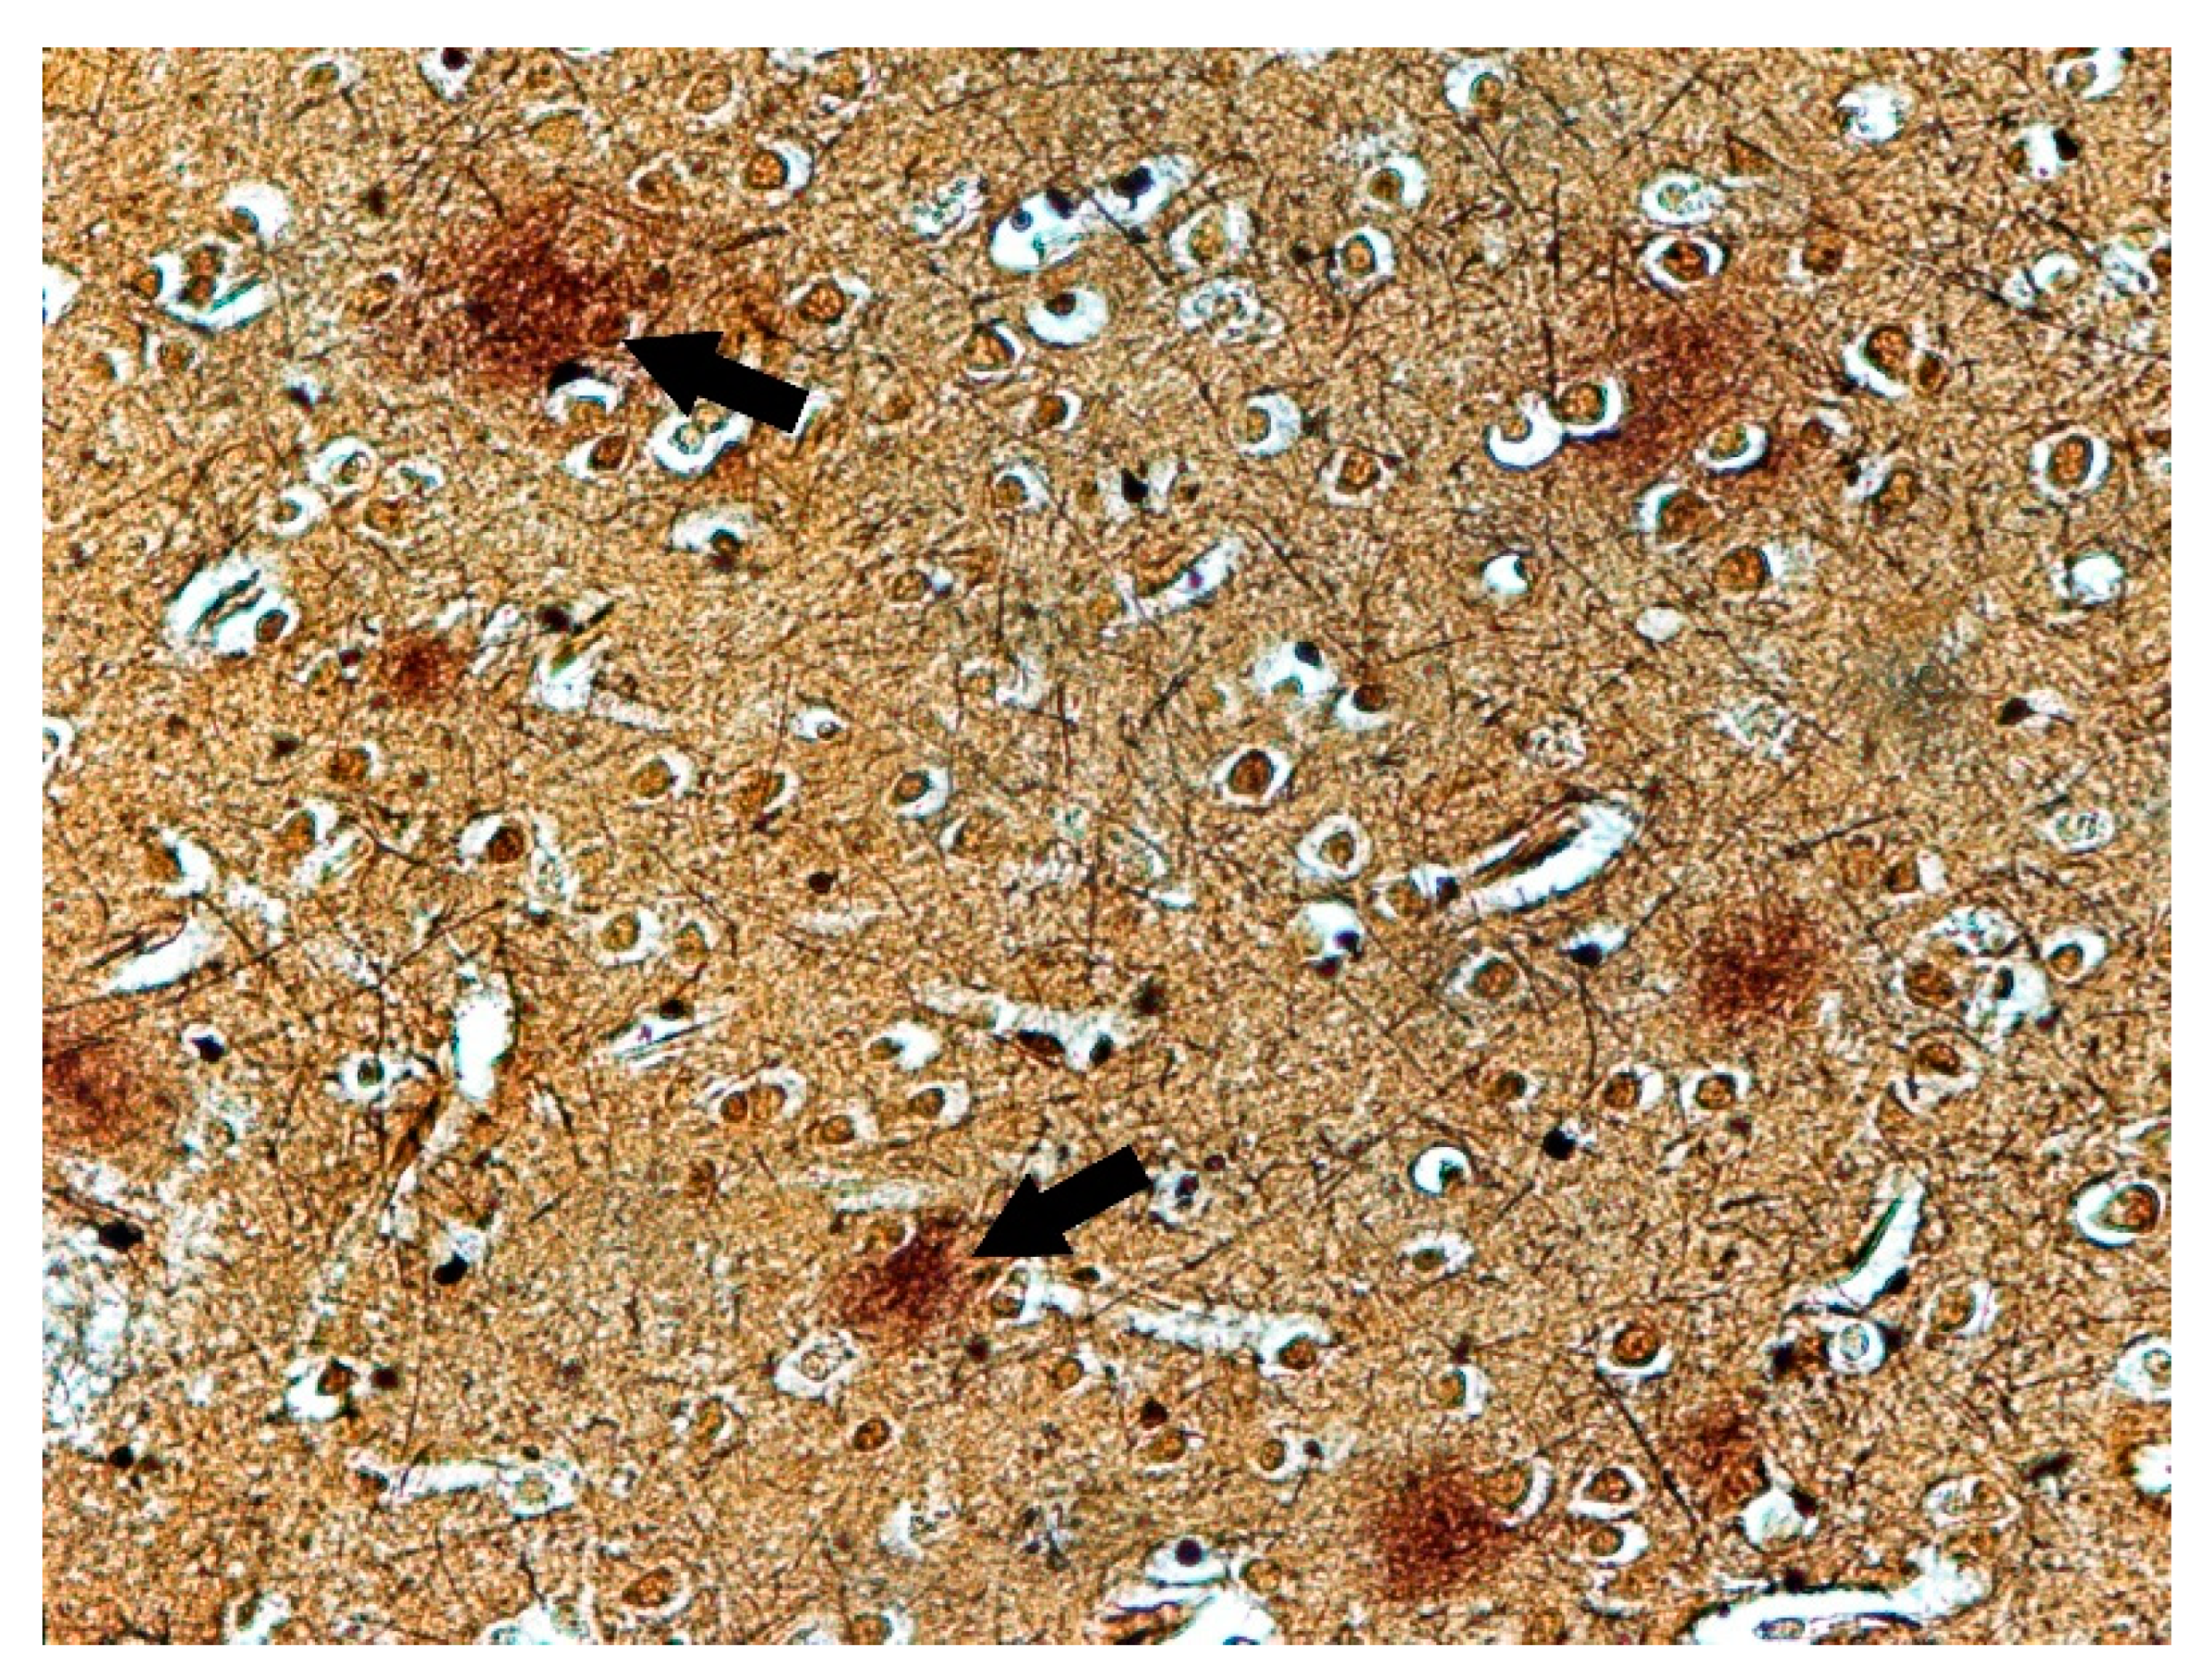

Histochemical Methods